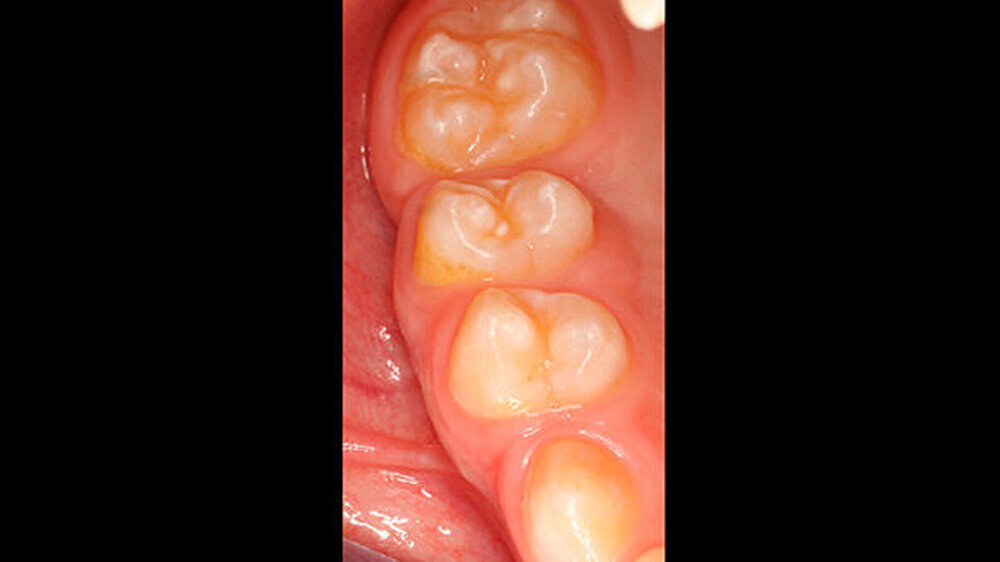

Der vor wenigen Jahren extrahierte Molar war der 16, anschließend war es im Laufe der Zeit im ersten Quadranten zu einer verhältnismäßig gleichmäßigen Lückenbildung gekommen. Der Zahn 17 war weitestgehend aufgewandert (Abbildung 2). Zahn 26 (Abbildung 3) wies eine umfangreiche adhäsive Restauration okklusal-bukkal auf. Zusätzlich dazu gab es aber auch weitere Areale mit veränderter Opazität von milchig-weiß (insbesondere palatinal) bis gelb-braun.